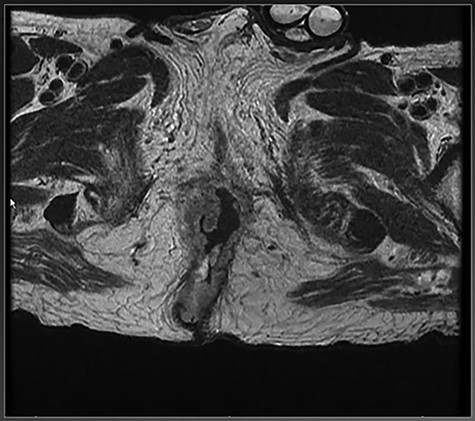

Multiple 4-mm punch biopsies were obtained which returned as BCC with nodular and infiltrative patterns. A computed tomography of the chest abdomen and pelvis was obtained that showed no evidence of metastatic disease. A magnetic resonance imaging (MRI) of the pelvis (Fig. 2) showed extension into the anal canal with complete loss of the external sphincter muscle and a majority of the internal sphincter muscle.

MRI of pelvis showing extension of tumor through the right external sphincter.